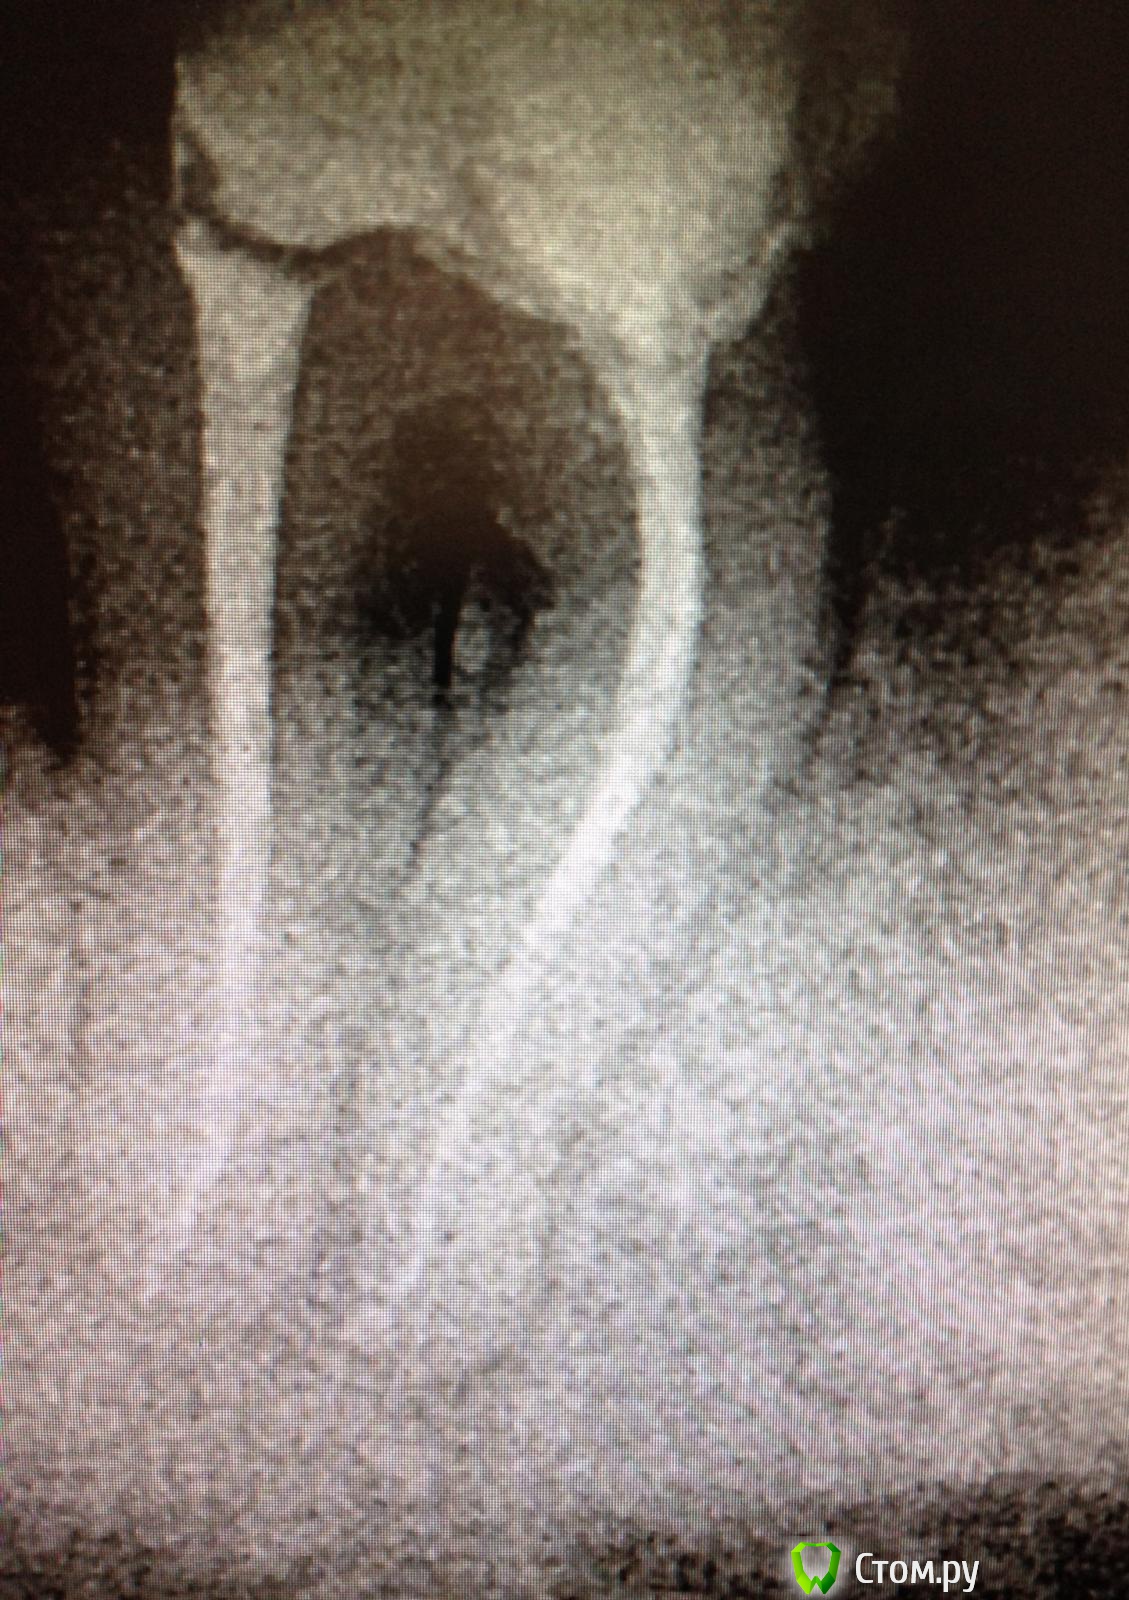

SSTi Опубликовано 2 июня, 2014 Автор Поделиться Опубликовано 2 июня, 2014 (изменено) Пришел парень с 36. Зуб болел при накусывании, прикасаться языком также было больно. Раньше лечен по поводу осложненного кариеса(пульпит). Пару дней назад ему убрали пломбу чуть прошли каналы и поставили времянку. Ему стало немного лучше. Сегодня пришел ко мне. Я делаю снимок, а там.....Анестезия, коффер, убираю времянку и из медиальных фонтанчиком получаю гной(никакого отека по переходной нет!). Прохожу щечный без проблем до f1, дистальный до f2, язычный то ли со ступенькой, то ли еще что то, но файл дальше 5 мм не шел. Потом десяткой взял чуть ближе к щечному и прошел. Очень долго мылись( 5 шприцев гипохлорита ) , гной подтекал минут 20. Уз. Эдта. Хлоргексидин. Кальций. Будем наблюдать пока....Снимки с файлами Изменено 2 июня, 2014 пользователем SSTi Ссылка на комментарий

Kivilgar Опубликовано 2 июня, 2014 Поделиться Опубликовано 2 июня, 2014 (изменено) Зуп покойник, эво как там расковыряли сильно устьевую треть каналаПервая фотка не грузится((( Чего там с фуркацией? Изменено 2 июня, 2014 пользователем Kivilgar Ссылка на комментарий

SSTi Опубликовано 2 июня, 2014 Автор Поделиться Опубликовано 2 июня, 2014 да видел я.... причем было запломбировано в дистальном только в расковыренной трети. Ссылка на комментарий

SSTi Опубликовано 2 июня, 2014 Автор Поделиться Опубликовано 2 июня, 2014 Чего там с фуркацией? с фуркацией ин рото все терпимо. перфо нет никаких Ссылка на комментарий

FoXx^_^ Опубликовано 2 июня, 2014 Поделиться Опубликовано 2 июня, 2014 А по первому снимку как-будто перфо по фуруации ближе к медиальным! Ссылка на комментарий

SSTi Опубликовано 2 июня, 2014 Автор Поделиться Опубликовано 2 июня, 2014 Это на снимке так. Я контрастность прибавил. Во рту нет перфо. Было бы-не стал бы браться Ссылка на комментарий